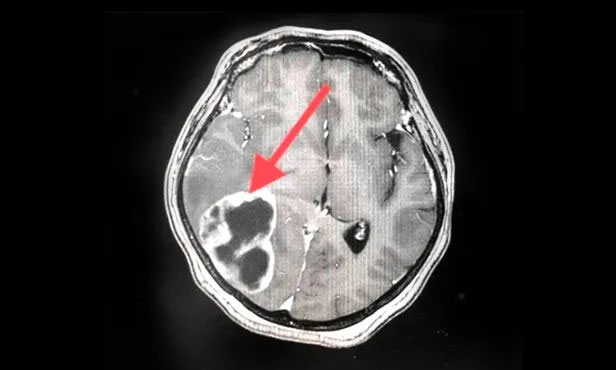

▲ 刚入院时病灶影像

▲ 完成穿刺,黑色囊液被顺利引流

▲ 经复查,病灶较前明显缩小

按照肿瘤复查的标准,复查影像显示王女士颅内病灶相较于来院时明显缩小。家属为此特意向陈琦主任致谢,并对医院的治疗和服务表达了充分肯定。